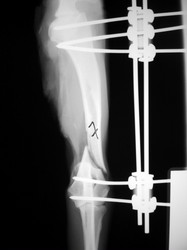

PRÁCTICAS CURSO DE FIJACIÓN EXTERNA PERFECCIONAMIENTO.

Húmero.